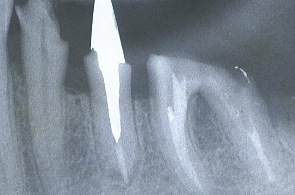

(症例T)審美歯科

セレモメタルクラウン装着

Cosmetic Dentistry Ceramiccrown for Mrs.Web

患者さまの過去の写真を参考に石膏模型上のワックスで最終的に入れるクラウンを再現。理想的な型を作り審美を追及した